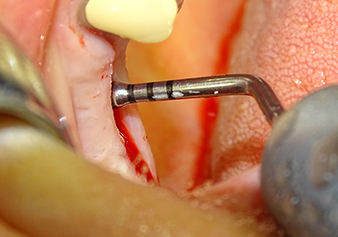

L’insert I2A (diamètre 2,0 mm) est ensuite utilisé pour perforer le plancher sinusien par intermittence et à la plus petite échelle possible. Cette méthode piézochirurgicale spéciale garantit que la membrane de Schneider n’est pas endommagée. Quand le Z25P est utilisé, la membrane est déjà légèrement relevée sous l’effet du fluide de refroidissement délivré via la pointe de l’insert (Fig. 3). Seulement 50 % du fluide de refroidissement sont éjectés afin d'éviter une pression élevée sur le site implantaire.

Préparation et augmentation du site implantaire